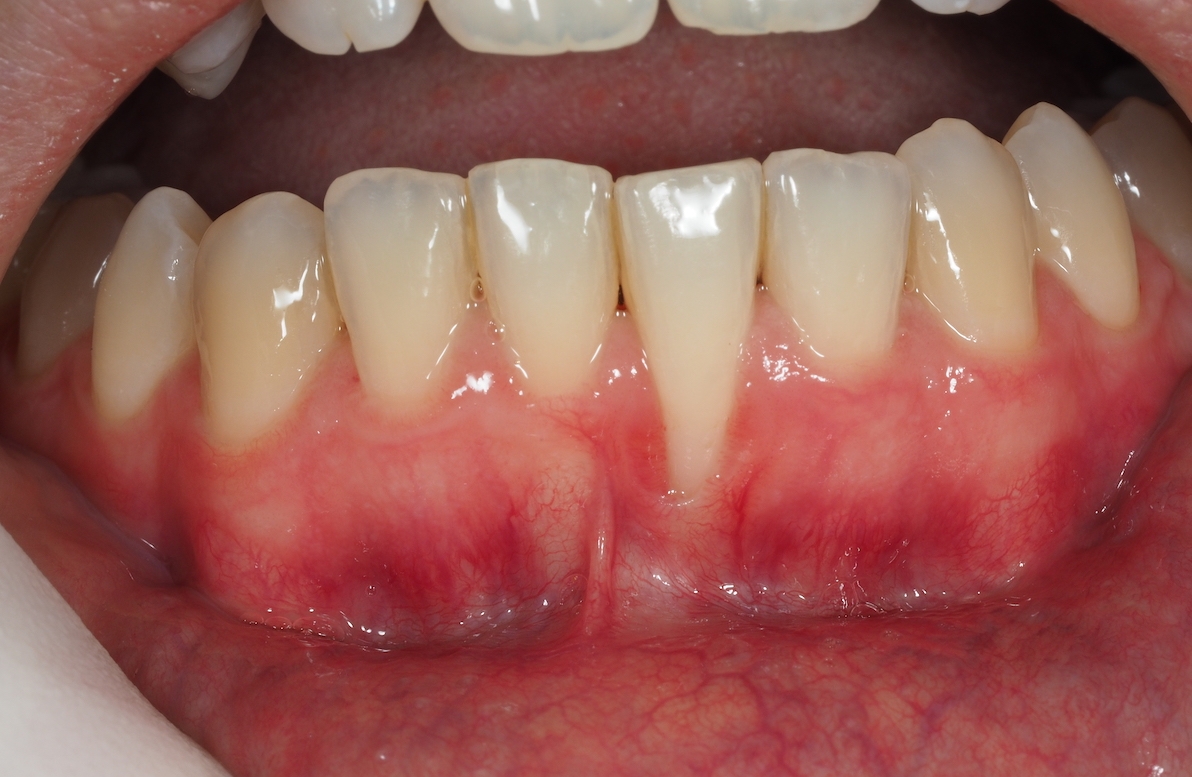

Una de las manifestaciones más frecuentes e iniciales es la gingivitis, un proceso inflamatorio de las encías que se muestran irritadas, inflamadas, enrojecidas y puede producir dolor y sangrado al cepillado con exudado purulento. Además, es habitual presentar halitosis o mal aliento.

Caso de Periodoncia 1 | Tratamiento Gingivitis

Después Después

Antes Antes